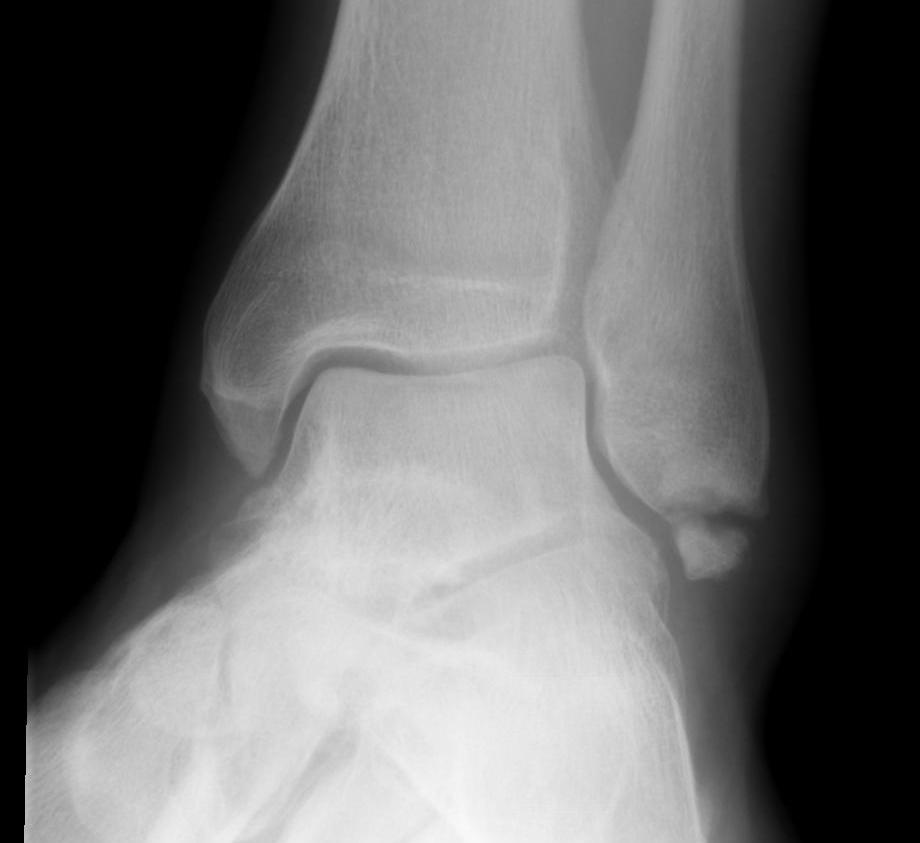

Fracture patterns

| Lateral malleolar fractures | Medial malleolar fractures | Bimalleolar fractures | Trimalleolar fractures |

Weber A - below syndesmosis Weber B - at syndesmosis Weber C - above syndesmosis |

Uncommon |

Fibular + medial malleolus Bimalleolar equivalent - fibular + deltoid ligament Fibular + posterior malleolus |

Fibular fracture + Medial malleolus fracture + Posterior malleolus fracture |